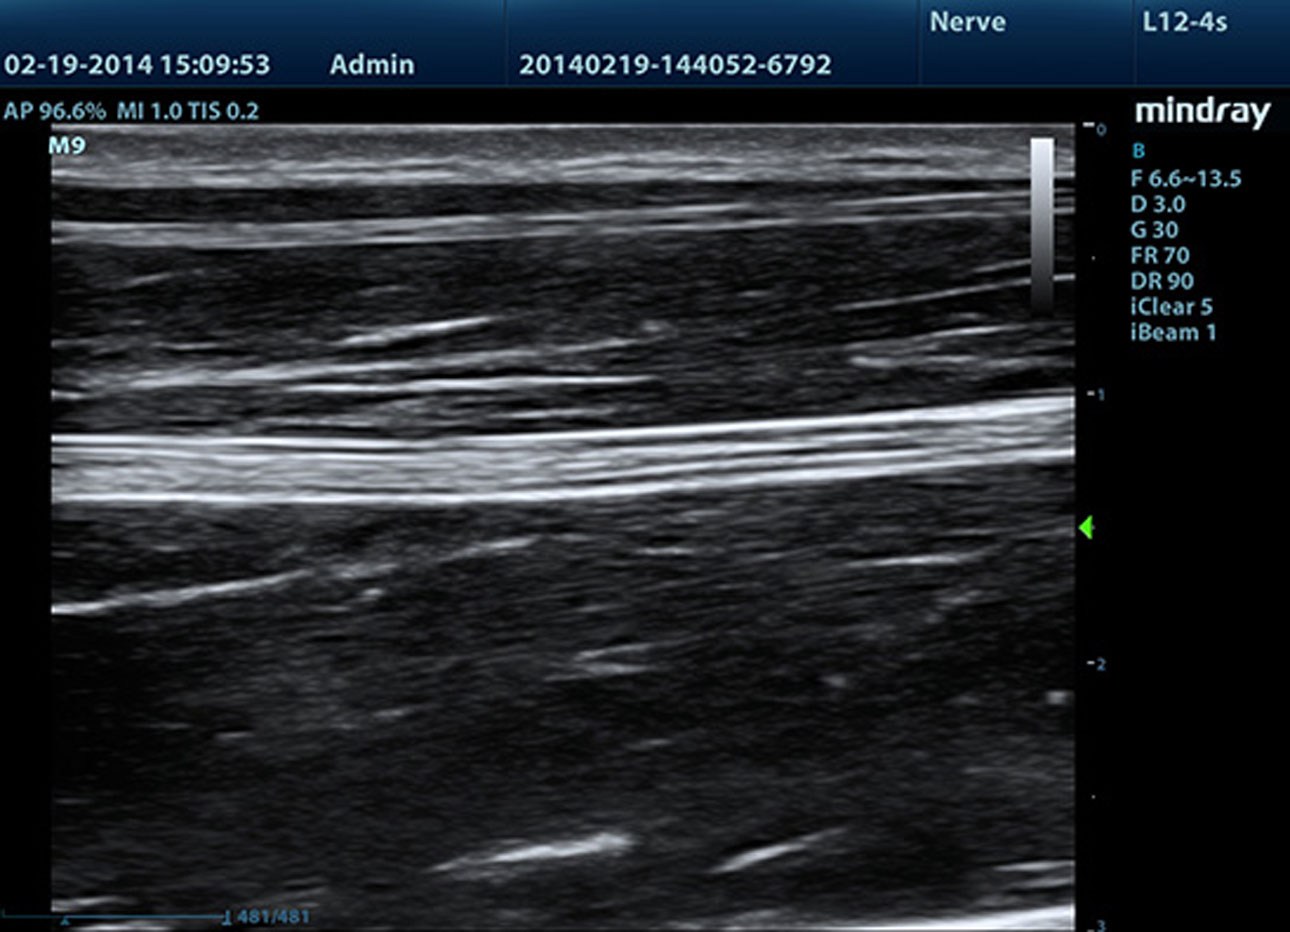

iNeedle??(Wzmocniona wizualizacja ig?y)

Funkcja ta polega na polepszeniu wizualizacji ig?y, co umo?liwia lepsz? widoczno?? ig?y, nawet podczas procedur przeprowadzanych pod ostrym k?tem z?jednoczesnym zachowaniem doskona?ej jako?ci obrazu. Dok?adniejsze potwierdzenie lokacji ig?y w?tkankach minimalizuje mo?liwo?? uszkodzenia s?siednich tkanek.